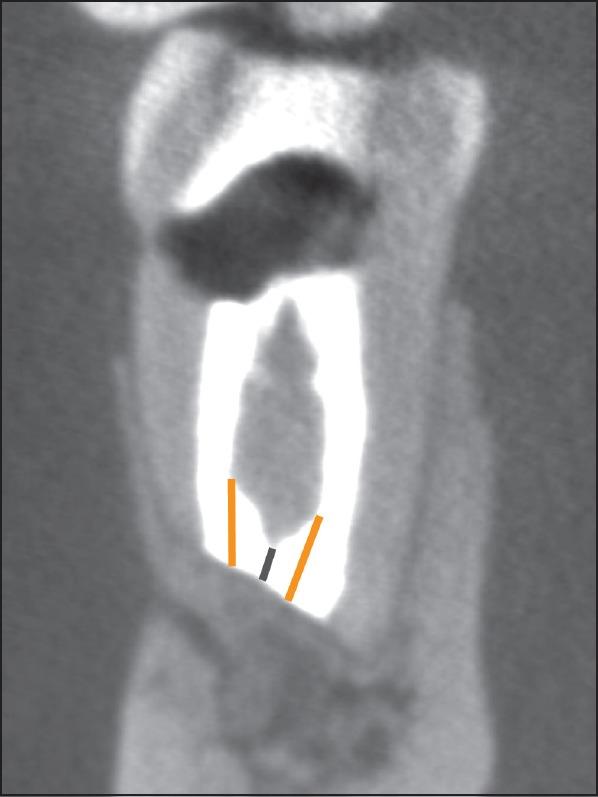

Cone beam computed tomography (CBCT) scans were utilized to measure the REF length and width and the PRD thickness in 61 roots of 53 teeth 1 year after apical surgery. Measurements were taken in the mesio-distal as well as bucco-lingual directions. The REF alignment with respect to the root axis was also evaluated. In addition, the dimensions of REF and PRD were assessed for possible correlations with the healing outcome. Criteria for determining the healing outcome included clinical and radiographic parameters.

The mean REF length was 2.02±0.52 mm. No significant differences were observed with regard to tooth groups, but one-canal roots had a significantly longer mean REF than two-canal roots (P=0.006). The mean REF widths were 1.14±0.24 mm mesio-distally and 2.61±1.24 mm bucco-lingually. Roots with two canals presented a significantly wider REF (P<0.001) in the bucco-lingual dimension but had a significantly narrower REF in the mesio-distal direction (P<0.001) compared to roots with single canals. PRD measured on average 1.19±0.23 mm at the resection level and 1.44±0.27 mm at the coronal end of the REF. Almost all REFs were perfectly aligned with the longitudinal axis of the roots. With regard to healing outcomes, no correlations were found with REF and PRD values, respectively.

REF的平均长度为2.02±0.52mm。在不同牙组之间未观察到显著差异,但单根管牙根的REF平均长度显著长于双根管牙根(P=0.006)。REF的平均宽度在近远中方向为1.14±0.24mm,在颊舌方向为2.61±1.24mm。与单根管牙根相比,双根管牙根在颊舌方向的REF显著更宽(P<0.001),但在近远中方向的REF显著更窄(P<0.001)。PRD在切除水平的平均测量值为1.19±0.23mm,在REF冠端的平均测量值为1.44±0.27mm。几乎所有REF都与牙根的纵轴完美对齐。关于愈合结果,分别未发现与REF和PRD值存在相关性。